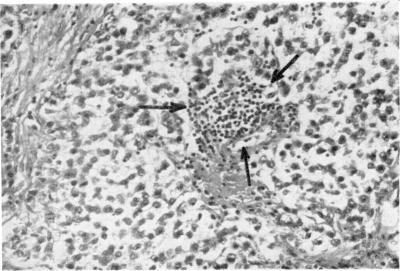

The simultaneous occurrence of a malignant ovarian dysgerminoma and of systemic lupus erythematosus is reported. The removal of the tumour resulted in a rapid disappearance of both clinical and biological symptoms of SLE. The possible relationship between tumours and autoimmune disorders is briefly discussed.

报告了一例同时发生恶性卵巢无性细胞瘤和系统性红斑狼疮的病例。肿瘤切除后,系统性红斑狼疮的临床和生物学症状迅速消失。本文简要讨论了肿瘤与自身免疫性疾病之间可能的关系。